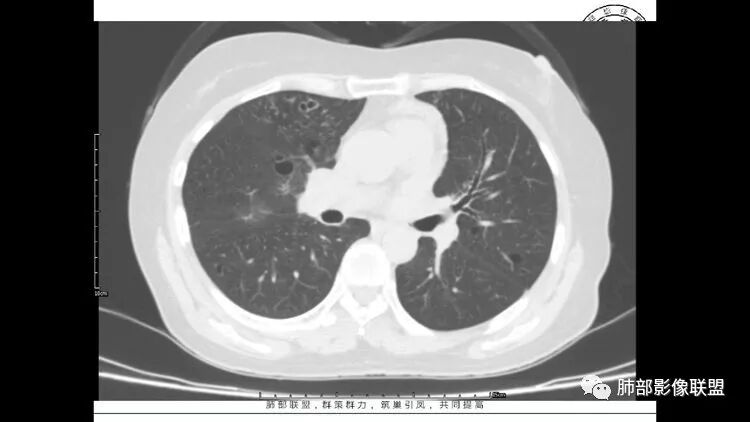

胸CT:1.双肺多发囊性变,以中下肺为主,病变边缘可见肺动脉,部分囊内可见分隔及肺动脉,双下部分肺野周围可见小叶中心结节及树丫征。

2 左肺上叶尖后段 右肺上叶前段 右肺下叶外基底段 结节影,边界清楚,可见柔软毛刺,左肺下叶后基底段混合密度影。

3.纵隔淋巴结肿大?,以主动脉弓为界向上向下增大。

患者中年女性,因右眼红痛1天就诊。胸CT:双肺多发囊性变及结节影,囊以中下肺为多,部分囊内可见分隔及肺动脉,结节部分为实性,部分为混合性,边缘光滑,未见明显毛刺、棘突、胸膜牵拉及血管集束征象。双中下可见支气管扩张及树丫征。淋巴结无明显肿大。综合考虑:一元淋巴细胞间质性肺炎。多元鉴别肺腺癌并转移等恶性病变。

中年女性,双肺多发囊性变,以中下肺为主,病变边缘可见肺动脉,部分囊内可见分隔及肺动脉,左肺上叶较大结节,可见分叶、月牙铲,左肺下叶、右肺中叶磨玻璃病灶,边界清楚,内有空泡,结节,可见尖后段 右肺上叶前段 右肺下叶外基底段 结节影,边界清楚,纵隔淋巴结肿大,

中年女性,因“角膜炎”入院,自用眼液2年,(眼干?)肺部:双肺多发类圆形薄壁气囊+实性结节+GGO,下肺分布为主,纵隔淋巴结肿大,考虑淋巴系统增殖,LIP可能性大,可能继发于干燥综合症;左肺下叶的混合磨玻璃结节形迹可疑,边界清晰,内部疑似空泡,扩张扭曲支气管,极像肺癌,伴双肺转移?待排吧

左肺下叶混杂密度病灶,其内可见空泡,周围ggo清楚,考虑浸润性腺癌。双肺散在多发薄壁囊腔和实性结节,以胸膜下及血管旁分布位于,气囊可见血管贴边征,双肺小叶间隔及中央间质增厚,局部可见磨玻璃影及树芽征,纵隔内淋巴结肿大,考虑LIP

综上,考虑左下肺浸润性腺癌+LIP

双肺多发大小不等囊腔,可见薄壁,部分囊腔内可见血管影,伴双肺多发结节,结合患者眼病及类风湿病史,考虑LIP可能大。另左肺下叶磨玻璃结节,边界清晰,内可见空泡,伴纵膈多发肿大淋巴结,不除外浸润性腺癌可能。

常规分析:右眼红疼1天,滴眼史两年,有类风湿病史,考虑有干燥综合征(SS)可能,需要了解自免抗体检测情况,双肺囊变需要考虑LIP,另右上叶前段GGO要鉴别腺癌或转移可能,右下叶背段多发树芽改变,双肺多发实性小结节,结核?左下肺混合性GGO考虑侵润性腺癌可能,双侧胸膜下多发结节,部分合并GGO改变,右侧腋窝及纵隔淋巴结多见,转移?最后问题来了,这个病人一元(腺癌合并转移,包括整个囊变,实性结节,胸膜下都是转移)?二元(LIP合并腺癌伴转移或者淀粉样变基础上的LIP)?三元(LIP+结核+腺癌伴转移)?

双肺多发散在斑片状磨玻璃密度影及大小不等的薄壁含气囊腔,下肺相对较多较大。双肺多发结节,界清,边缘光滑,分叶不明显。右肺下叶前外基底段散在斑片树芽。前上纵膈偏左侧不规则软组织团块,密度不均,其内可见不规则纤维样低密度,周围簇状小淋巴结。考虑1淋巴细胞间质性肺炎。2考虑纵膈胸腺淋巴瘤。

LIP影像重要线索一句话:

双肺下叶分布为主的间质改变(磨玻璃影、小叶间隔增厚)、散在气囊影(常有血管贴边)、边界不清小结节